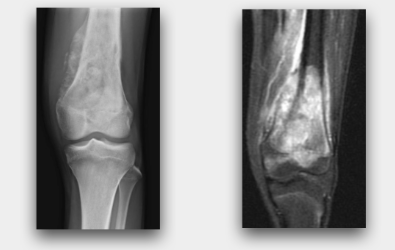

以下的病例,為我們一位14歲遠端股骨骨肉瘤的孩子,我們給予廣泛性腫瘤切除後,再進行生物性重建合併人工關節的重建。

一:病患手術前X光與MRI。顯示腫瘤位於膝蓋上方,並侵犯至生長板與骨骺。